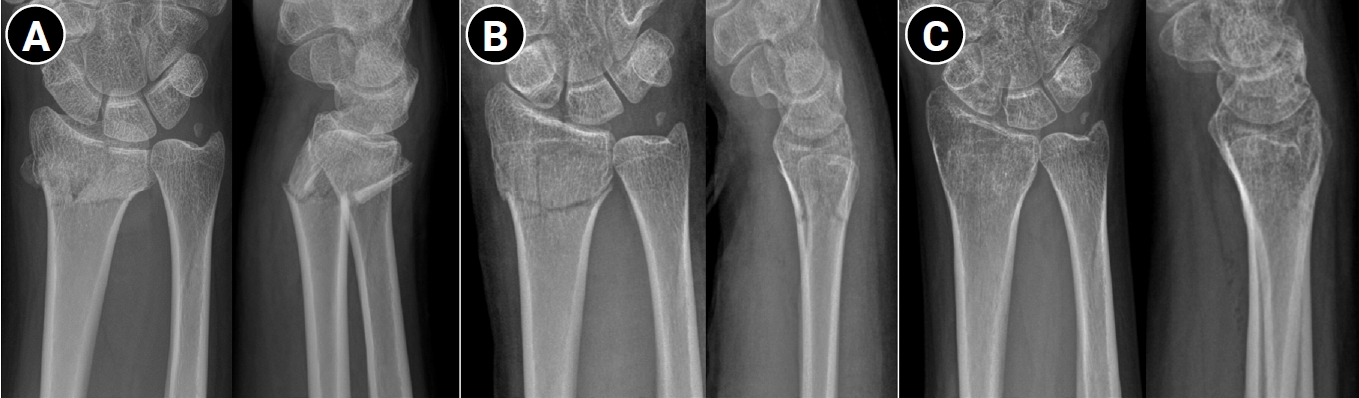

Radiographic criteria for determining whether to proceed with operative treatment after successful reduction have also been extensively studied. With advances in surgical techniques and implants, operative treatment has shown improved outcomes, narrowing the indications for conservative management, especially in younger patients with high functional demands. Radial shortening of >2 mm, DRUJ subluxation, and significant anteroposterior translation of the distal ulna are generally considered unsuitable for conservative treatment. However, acceptable thresholds for intraarticular incongruity (<1 mm vs. <2 mm) and dorsal tilt (allowing up to 10° vs. allowing only neutral alignment) remain controversial (Fig. 1) [15-19]. Randomized controlled trials comparing conservative and operative treatment for displaced distal radius fractures have consistently demonstrated superior radiographic alignment following surgical fixation, particularly with respect to volar tilt and radial inclination at final follow-up [20]. Several studies have also reported modest advantages in early functional recovery and grip strength in surgically treated patients during the initial postoperative period [21,22]. However, long-term follow-up data in elderly populations indicate that these early advantages do not persist over time. Large prospective studies have shown that although volar locking plate fixation may facilitate faster early recovery, it does not confer superior patient-reported outcomes at 12 months when compared with cast immobilization [23,24]. In line with these findings, a comprehensive systematic review and meta-analysis by Gutierrez-Espinoza et al. [25] concluded that while statistically significant differences in radiologic and functional outcomes favor volar plate fixation, these differences do not exceed minimal clinically important difference thresholds. Furthermore, ulnar variance did not differ significantly between treatment groups, and radiographic parameters showed limited correlation with long-term clinical outcomes (Table 1) [20,22,24,26-28]. Collectively, these data suggest that despite the potential for radiographic malunion in conservatively managed cases, long-term functional recovery is not inferior to surgical intervention, supporting nonoperative management as a viable primary treatment option.

Fig. 1.

Successful conservative treatment of a displaced distal radius fracture in a 20-year-old female patient. (A) Immediate posttrauma wrist anteroposterior and lateral radiographs demonstrating a dorsally displaced intraarticular distal radius fracture of the right wrist. (B) Wrist radiographs obtained after manual reduction, showing restoration of volar tilt and radial length. (C) Wrist radiographs at 3 months posttrauma, demonstrating maintenance of fracture alignment and satisfactory fracture union.

Fig. 1. Successful conservative treatment of a displaced distal radius fracture in a 20-year-old female patient. (A) Immediate posttrauma wrist anteroposterior and lateral radiographs demonstrating a dorsally displaced intraarticular distal radius fracture of the right wrist. (B) Wrist radiographs obtained after manual reduction, showing restoration of volar tilt and radial length. (C) Wrist radiographs at 3 months posttrauma, demonstrating maintenance of fracture alignment and satisfactory fracture union.